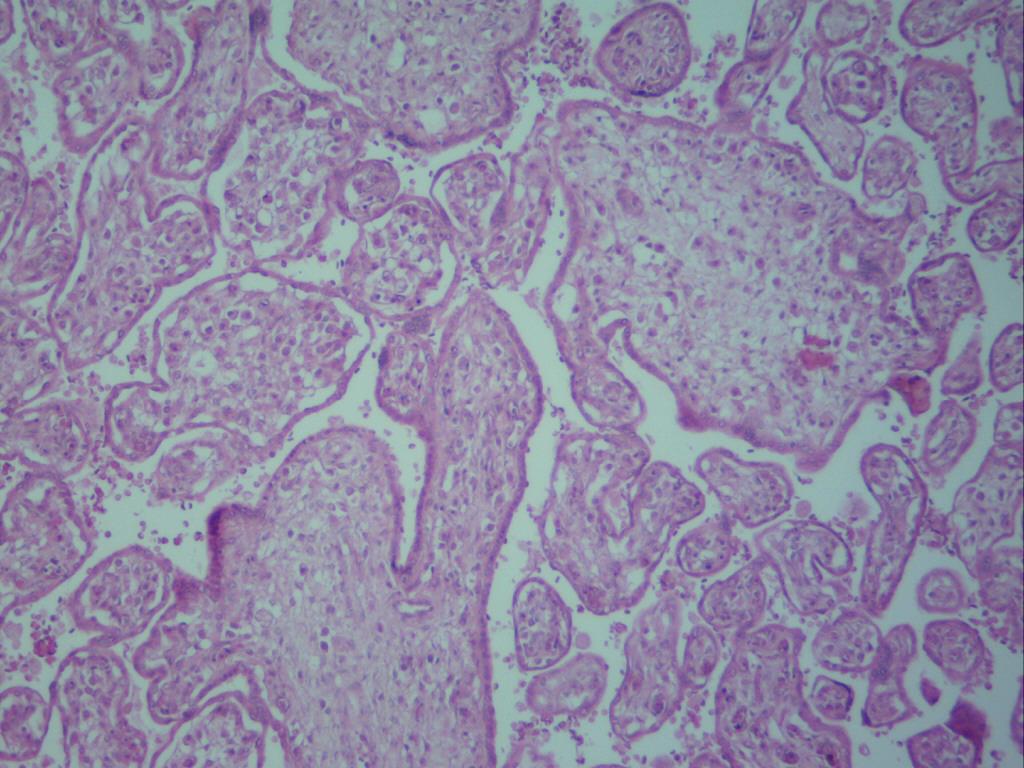

While in presence of a term placenta, strikingly numerous and barely ramified immature intermediate villi - corresponding more to earlier stages of gestation - were observed (Fig.1). Zones of infarction and calcification, fibrinoid necrosis and retroplacental hematomas were visualized. No chorangiosis was noted. A prominent and well-developed cytotrophoblast was present.

Fig.1 A generalized vision of placental villi where immaturity and edema are noticeable 100X.

Placental villi were not surrounded by intervillous thrombosis. Some of them revealed vessels in the stromal region decreased in quantity. In immature intermediate villi a thinner trophoblast with interruptions and poor ramification was noted (Fig.2). In these villi impaired endothelial and muscular layer of vessels, and vessels tending to be closed or just disappearing, were noted (Fig. 3).

To sum up, morphology of placental villi was usually as that observed in the upper left corner of Fig. 1, all of them edematous.